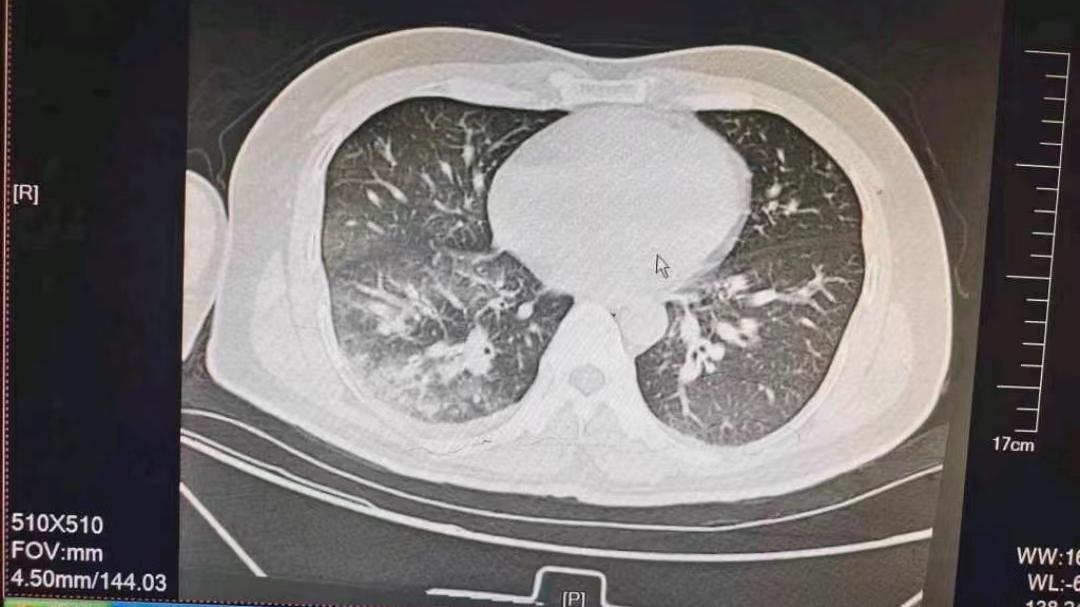

很多的男性朋友在平时都有抽烟的习惯 , 有些人是为了工作应酬而不得已选择抽烟 , 但是有些人也是用抽烟来缓解一下自己的心理压力 。 但是吸烟对身体的健康是非常有害的 , 它含有丰富的尼古丁 , 这种物质对肺部的危害非常的大 , 如果长期吸烟的话 , 肺部很可能会产生各种疾病 , 很容易引发肺癌 。 它是尼古丁“克星” , 经常吃 , 排出烟毒 , 让你不用戒烟肺也舒服些